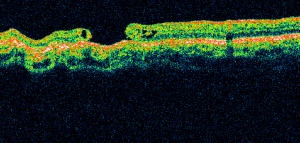

Cystoid macular edema (CME):

Cystoid macular edema can be seen on OCT scans as multiple circular or oval hypo-reflective spaces in the retina, indicating intraretinal edema.

Serous macular detachment (SMD) with cystoid diabetic macular edema (DME) shows retinal elevation with an optically clear space between the sensory retina and the retinal pigment epithelium.